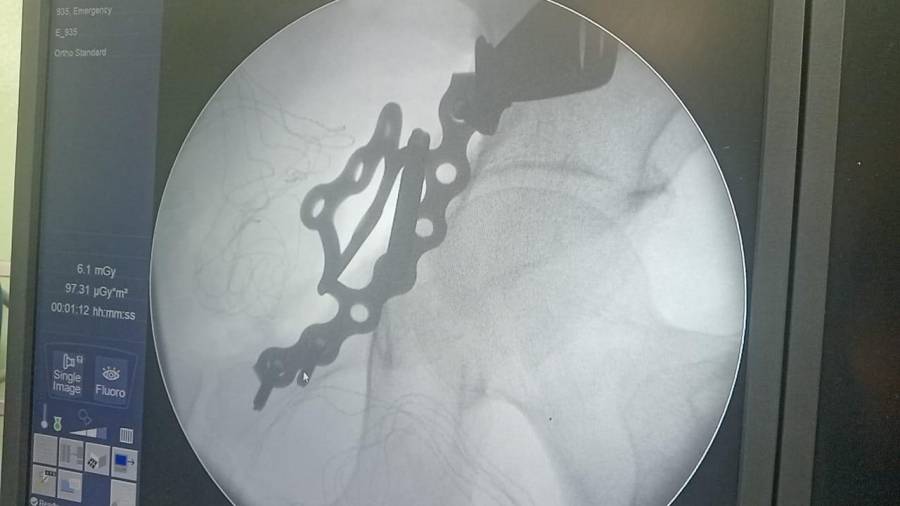

- إجراء عمليات جراحية معقدة و دقيقة في مجال العظام و المفاصل و الكسور و الإصابات ، رغم الضغط الكبير على المستشفى و أعداد المراجعين الكبيرة.

- تطبيق تقنيات جراحية حديثة و متقدمة، و ذلك في ظل التحديات التي يواجهها الفريق بسبب أعداد المرضى و المراجعين الكبيرة.

- تقديم خدمات جراحية عالية الجودة و آمنة للمرضى، رغم الضغط الهائل على المستشفى في العيادة و القسم و الطوارئ .